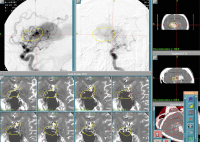

Gamma-Knife-Behandlung

Abbildung 3: Gamma-Knife-Behandlung: Zur bestmöglichen Darstellung der zuführenden Feeder werden stereotaktische Angiographie-, MRT- und CCT-Bilder angefertigt. Dies ermöglicht eine gezielte Bestrahlung mit konsekutiver Endothelzellproliferation und Gefäßverschluss nach Monaten bis Jahren (Bildmaterial dankend zur Verfügung gestellt von Dr. Gatterbauer, Univ.-Klinik für Neurochirurgie, AKH Wien)

Keywords: AngiographieCCTGamma-Knife-BehandlungMRTTherapieVena-Galeni-Malformation